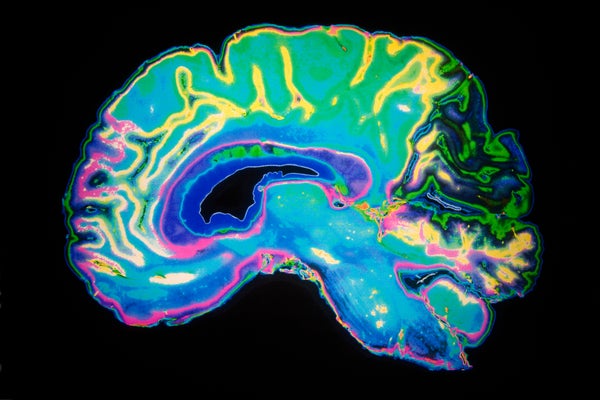

The connections in my mind is really – it's suggestibility and it's expectation. That's at the heart of my book is your brain is – at its core, it's a prediction machine. This is something that artificial intelligence people have been saying for a long time. Everything it does all day long is creating predictions and to make life easier and to use the past to apply to the present in order to predict what's about to happen.

Vance: Yeah. My one-year-old baby has not gotten that lesson. So, I think that's also an experience kind of thing because he just crawls off whatever he sees. But this is what our brain does. In the process of doing that, it creates – it's an expectation generator. It creates these expectations. What's interesting about them is when your expectation and reality don't match, sometimes the brain will step in and make expectation reality.

Vance: I felt it less and my foot didn't twitch. I mean it wasn't that I was reporting feeling it less. I really felt less pain. It's because I created expectations for what green and red meant. When expectation didn't meet reality, my brain stepped in and released drugs in order to bring down that pain so that it fit with the expected or at least close to what it expected.

That's what's at the heart at a lot of these placebo effects. It's your brain trying to get expectations to meet reality. I think of the brain as sort of a bureaucrat. He's got paperwork to fill out and he doesn't care what happened. He just wants to make sure the paperwork fits.